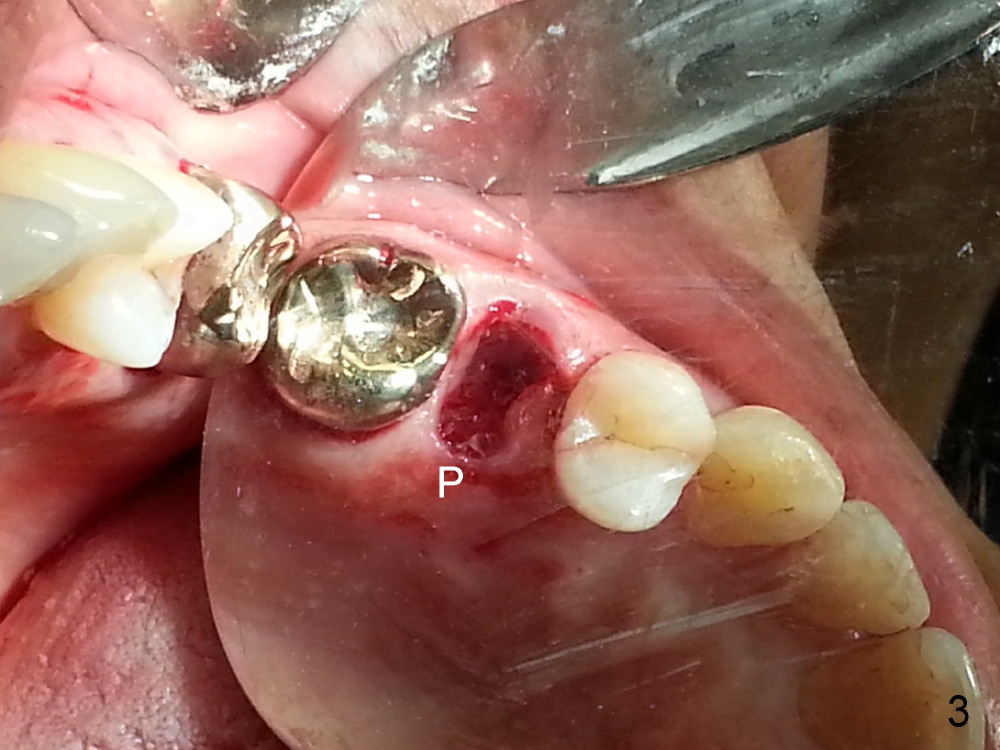

The tooth #13 appears to be affected by periodontits and occlusal trauma (Fig.1*). After using a periotome (Fig.2), the tooth is extracted (Fig.3). The buccal flap is raised (Fig.4). Gingival graft is to be harvested from the site of #15 (Fig.5). The tissue is elevated buccally (Fig.6) and separated (Fig.7). The donor site is covered by a collagen membrane (Fig.8*). A diamond bur is used to induce bleeding from the socket (Fig.9*). Osteotomy is initiated (Fig.10) and enlarged (Fig.11,12). A tapered implant is being placed (Fig.13-15) following internal sinus lift (Fig.16,17). The implant is placed subcrestally, followed by bone graft (Fig.18), soft tissue graft (Fig.19), and suturing (Fig.20 <, Fig.21).